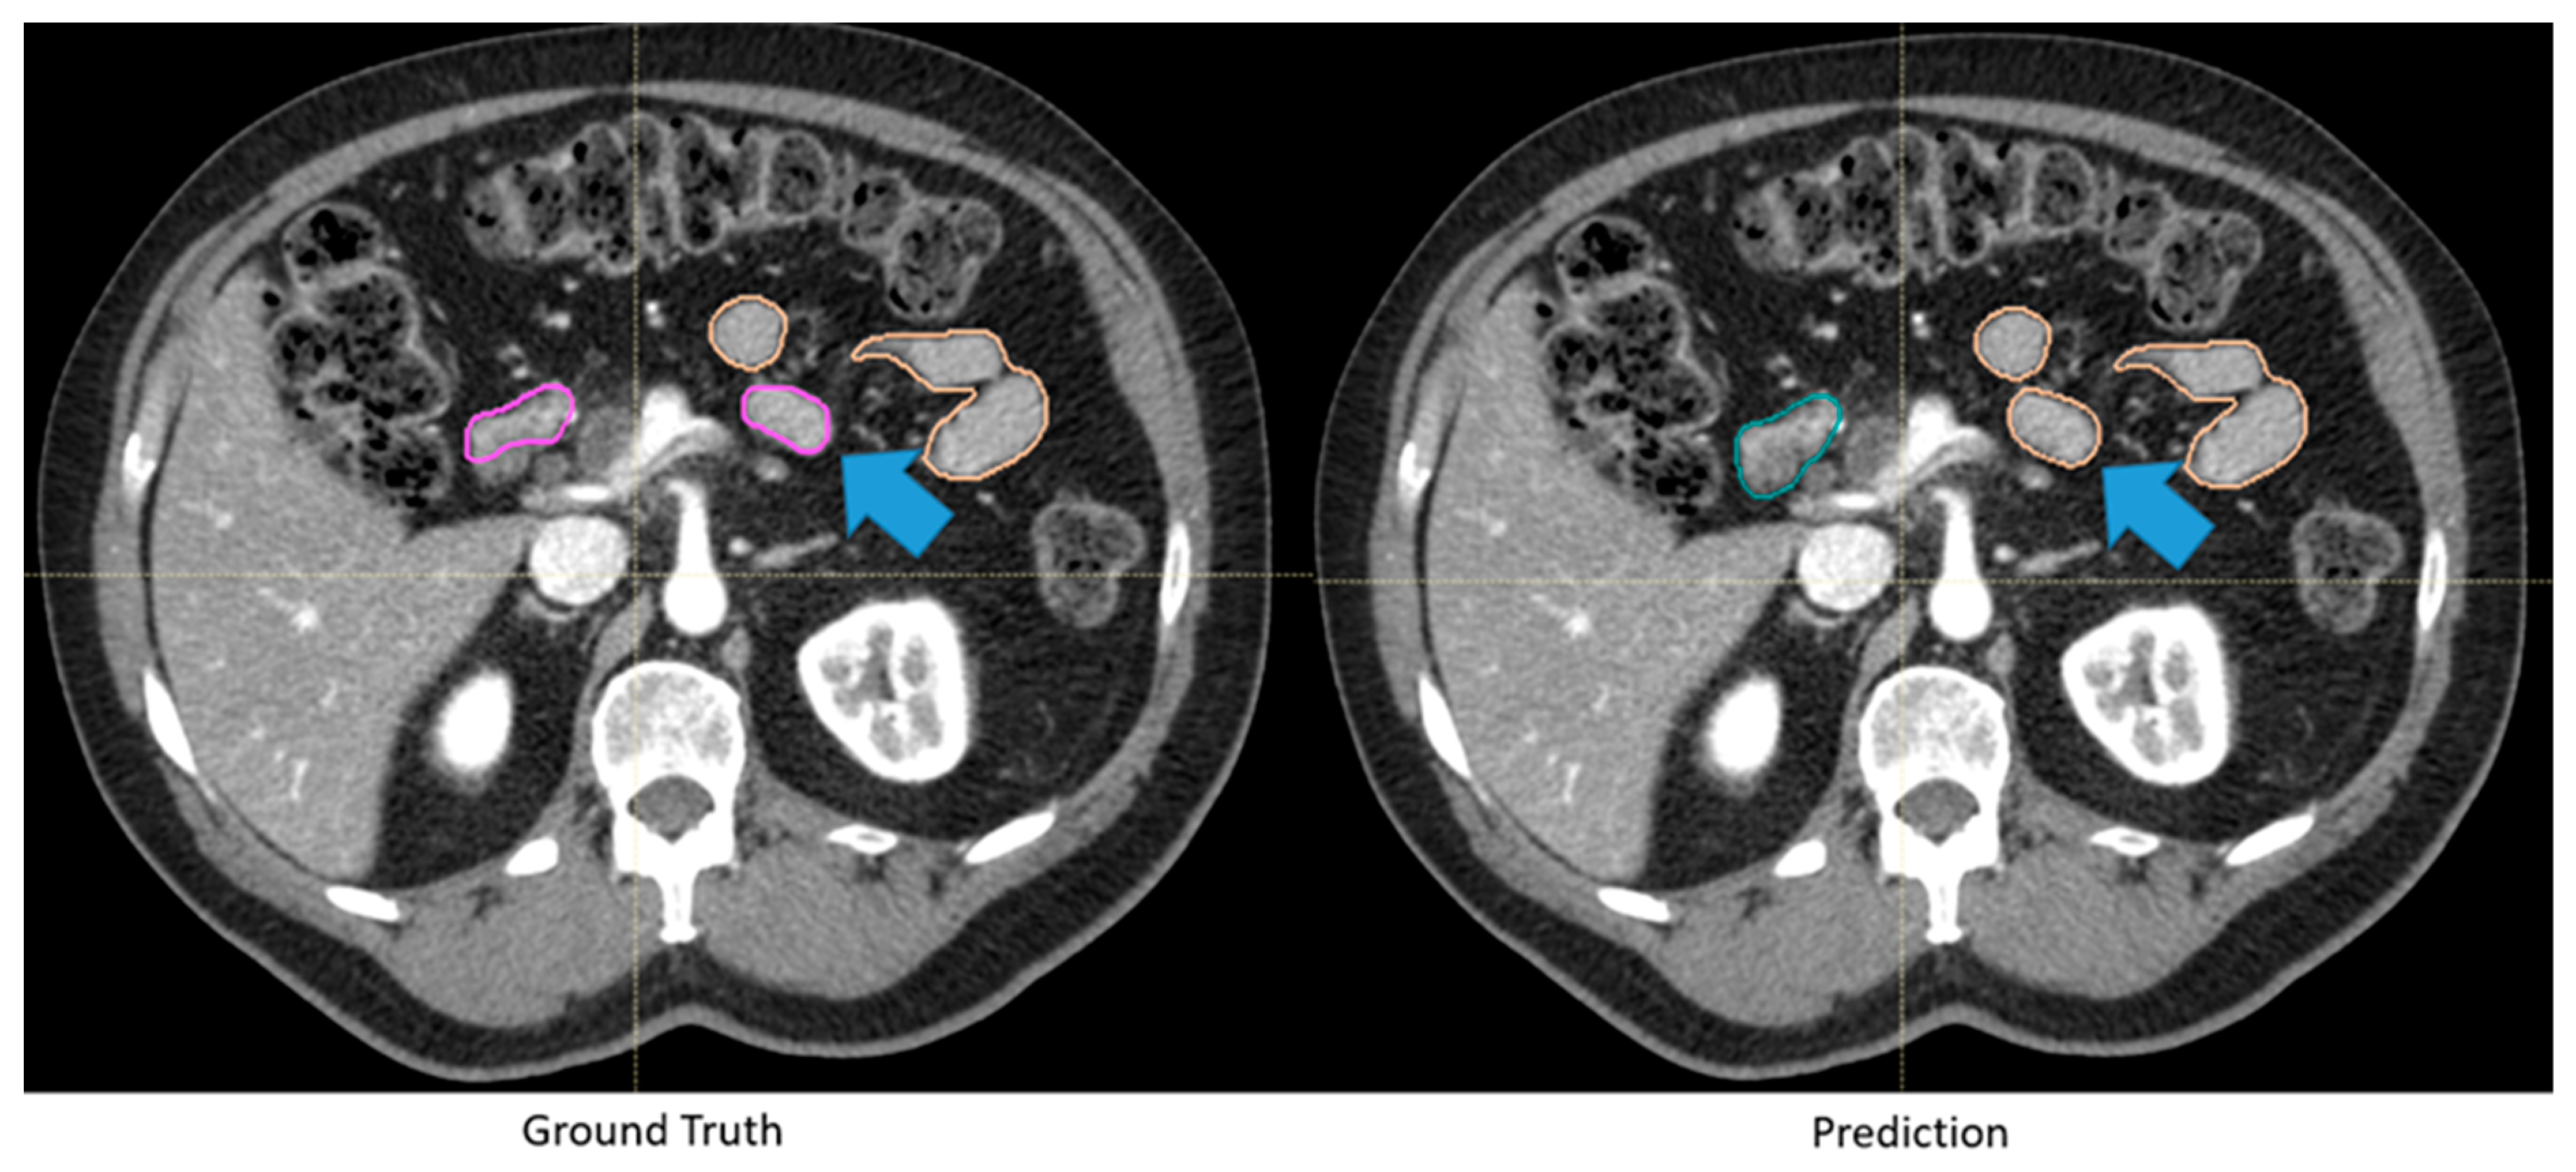

Figure 2.

Automatically generated duodenum and small bowel contours with low Dice similarity coefficient (0.61) but were deemed clinically acceptable. Although the automatically generated contour (green: duodenum, yellow: small bowel) deviated from the “ground truth” (pink: duodenum, yellow: small bowel), as highlighted by the blue arrows, the difference was deemed insignificant by clinicians because of the identical dose constraints between the two segmented organs.